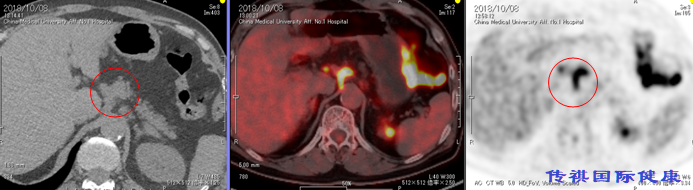

2018年10月复查,PET CT确诊肺腺癌3A期术后多发转移。但因胃小弯侧及腹膜后膜主动脉旁多发淋巴结影(最大SUV10.2较2017-09-21,病灶增多,代谢增高),紧邻胃壁,很难接受国内传统放疗,极易引发胃穿孔,同时多发转移无法手术,仅考虑化疗,但不排除化疗药物出现耐药性后病情恶化。

A: 1-4。从胃上部大弯侧淋巴节到腹腔动脉干右侧的淋巴节可见不规则的如同姜根状的连续肿大淋巴结,该部位FDG呈现集聚。淋巴节有转移巢的可能性。

B: 5 . 可见上肠间间膜动脉处右侧大动脉淋巴节的FDG集聚。淋巴节有转移巢的可能性。

C: 6和7,.在气管分歧周围的淋巴节上可见FDG集聚。淋巴节有转移巢的可能性。